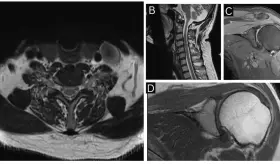

Tras múltiples evaluaciones cardíacas normales, estudios de imagen revelaron un schwannoma espinal a nivel D6-D7 como causa del dolor torácico neuropático.

La paciente fue diagnosticada con endometriosis del nervio ciático derecho tras años de dolor incapacitante y diagnósticos erróneos.